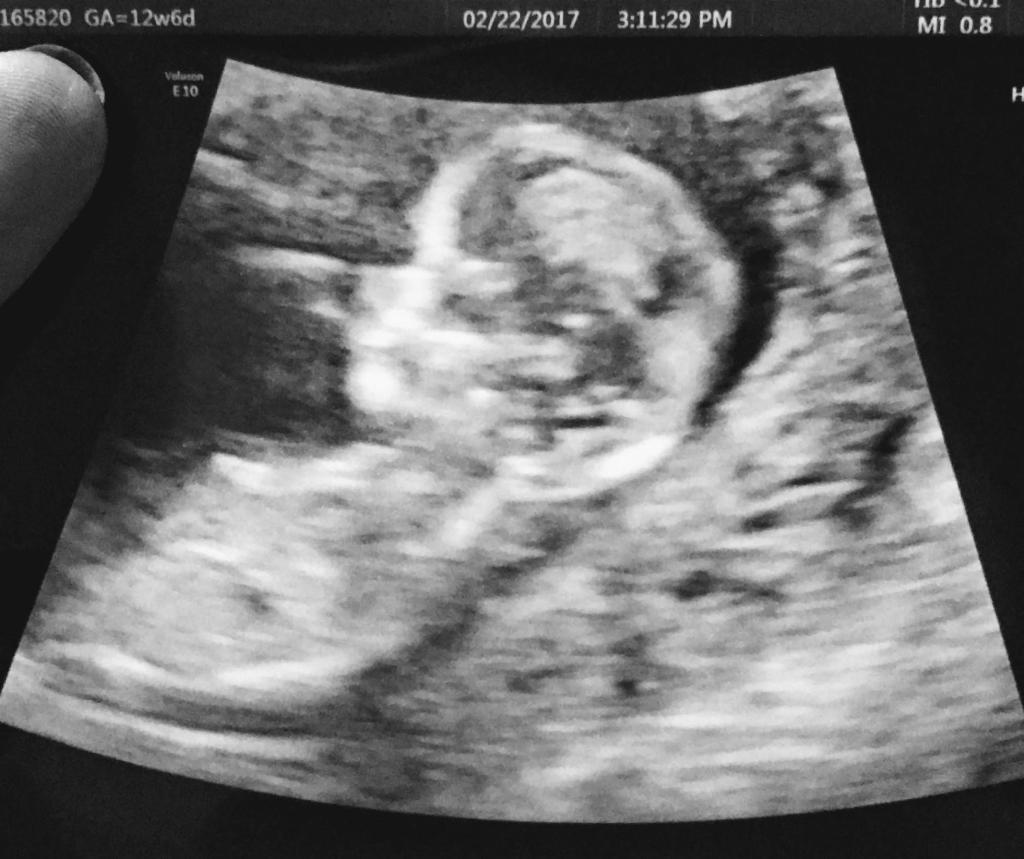

Mi Primer Trimestre

Mis travesías en mi primer trimestre de embarazo. Nada fácil pero si se pudo:). Incluyo también las cosas que compre en las primeras 14 semanas.